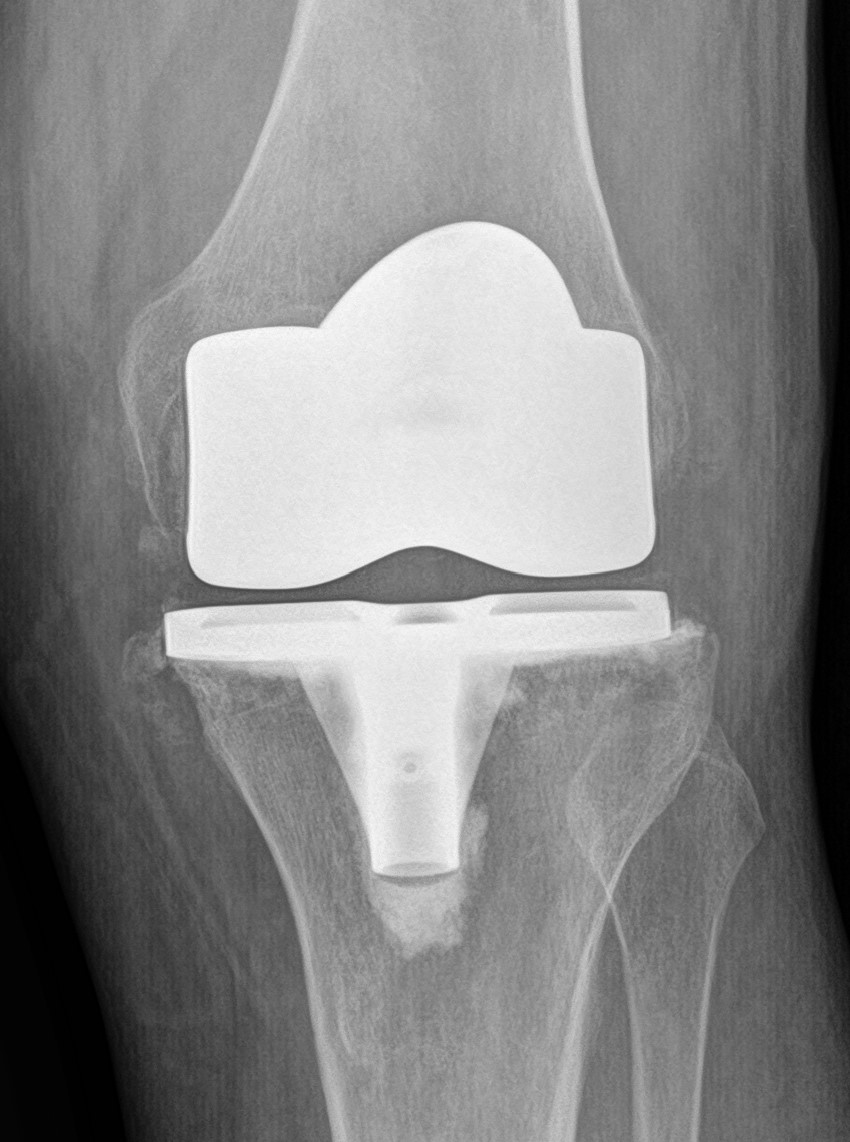

@Itx_moana Here's mine, the one in the video is a partial which is just 1 side of 1 knee joint. I had a full so it's kinda like two partials put together.